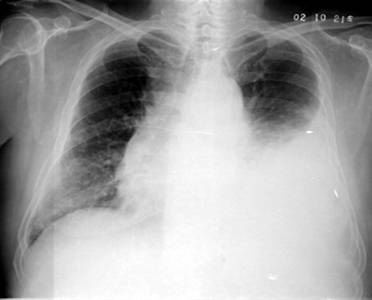

照片名称:大量胸腔积液